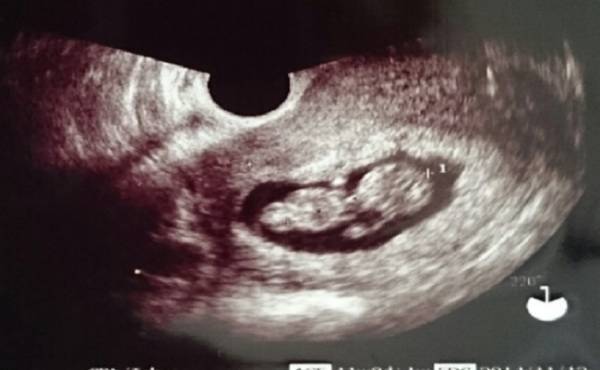

妊娠7カ月、赤ちゃんの心臓病が見つかった

毎回、妊婦健診でおこなう超音波検査。最近では、4D画像も見ることができて、ママにとっても赤ちゃんが見られるうれしい時間ですよね。このエコー、先生が見ているのは胎児の推定体重や性別だけではありません。

白黒の映像の中でも見ることのできる内臓や血管があり、異常がないか先生は見ているのだそうです。

私は妊娠7カ月のころ、赤ちゃんの心臓病が見つかりました。エコーではっきりと、心臓の中の形が見えたことを覚えています。